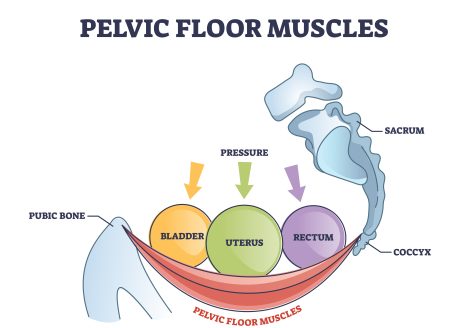

5 Signs You Need Pelvic Floor Physical Therapy

Danielle Ivie, DPT, CSCS | Founder of Powered by Movement Physical Therapy What is pelvic floor physical therapy? Great question! Pelvic floor physical therapy is exactly what it sounds like – rehab…

Get Rid of Your Low Back Pain with Pelvic Floor Muscle Training

Danielle Ivie, DPT, CSCS | Founder of Powered by Movement Physical Therapy Imagine this scenario: You work out regularly, usually feel pretty good, but every few months or so your back tightens…